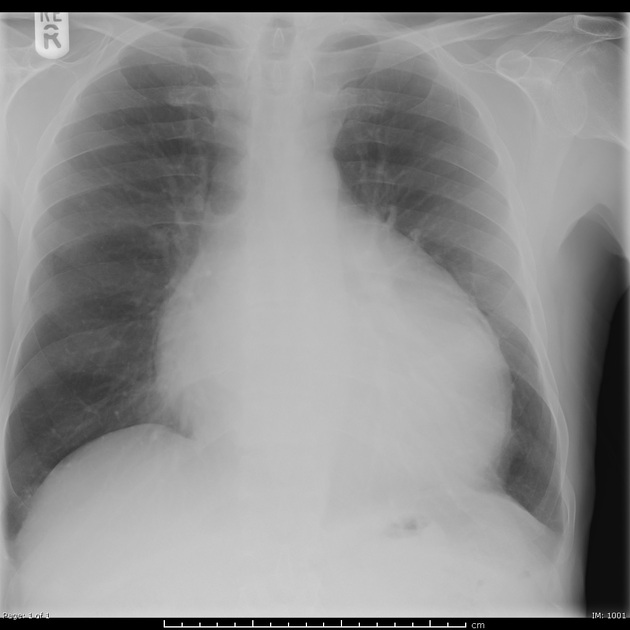

Enlarged, globular cardiac silhouette indicative of a pericardial effusion.

Describe the abnormality demonstrated.